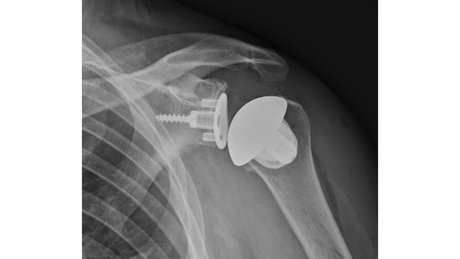

Therapieoption: Implantation einer anatomischen/inversen Schulterprothese

Die Implantation einer Schulterprothese kann bei Arthrose im Schultergelenk, der sogenannten Omarthrose, nötig werden. Hierbei kann man zwei verschiedenen Formen der Arthrose unterscheiden:

In einem Fall ist die Rotatorenmanschette, also die umgebenden Sehnen an der Schulter, welche die Stabilität und Beweglichkeit des Gelenkes gewährleisten, intakt. Der Knorpel ist jedoch aufgebraucht. Bei der Implantation einer Prothese werden die Gelenkpartner ersetzt und deren Form wird beibehalten. Eine sogenannte anatomische Schulterprothese wird implantiert.

Sollte die Rotatorenmanschette, also die umgebenden Sehnen an der Schulter, welche die Stabilität und Beweglichkeit des Gelenkes gewährleisten, nicht mehr intakt sein, dann ist ein anderer Prothesentyp nötig. Hierbei ist die Prothese so aufgebaut, dass sie durch Umkehr der Gelenkformen, die Funktion der fehlenden Sehnen übernimmt. Die flache Pfanne wird sphärisch und der ursprünglich runde Kopf wird als Schale implantiert. Dadurch kann man trotz fehlender Rotatorenmanschette die nötige Stabilität und Beweglichkeit des Schultergelenkes wiederherstellen. Eine sogenannte inverse Schulterprothese wird implantiert.

Sollte bei Ihnen eine Prothesenimplantation durchgeführt werden, sind unter Umständen zuvor verschiedenen bildgebende Verfahren nötig um die korrekte Prothese auswählen zu können.

Bei allen Prothesenformen gibt es verschiedenen Designs. Insgesamt versucht man so knochensparend wie möglich zu operieren. Das bedeutet viel vom eigenen Knochen zu erhalten. Schaftlose Prothesen und kurze Schäfte werden daher bevorzugt. Bei vorbestehender eingeschränkter Knochenqualität kann zur Aufrechterhaltung der Stabilität eine etwas längere Verankerung im Knochen notwendig sein.

Insgesamt ist wichtig, dass man individuell entscheiden muss ob eine Prothese implantiert wird und welche Form der Prothese gewählt wird.

Üblicherweise schließt sich an die Operation eine 5-6 wöchige Nachbehandlung ohne Kraftaufwendung am Arm an. Im Anschluss ist die Prothese gut eingeheilt und man kann mit einer Belastungssteigerung starten. Dies erfolgt üblicherweise im Rahmen eine Rehabilitation, welche bei der Festlegung des Operationstermins, vorab reserviert werden kann.

Auch Revision einer vorhandenen Schulterprothese, die Konversion von anatomischer Prothese auf eine inverse Prothese, partieller Wechsel oder gesamter Wechsel werden angeboten und durchgeführt.